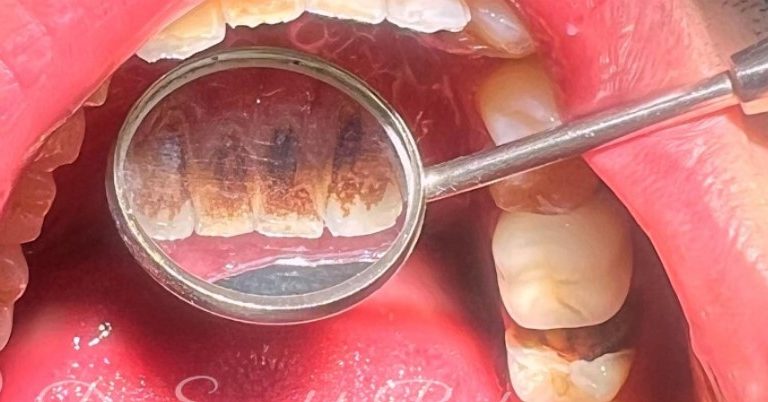

جرمگیری دندان یکی از خدمات مهم بهداشتی و درمانی در دندانپزشکی است که به حذف پلاکها، جرمهای سختشده (تارتار) و رنگدانههای سطحی روی دندانها و اطراف لثه کمک میکند. این جرمها معمولاً با مسواک و نخ دندان پاک نمیشوند و با گذشت زمان باعث التهاب لثه، خونریزی و بوی بد دهان میشوند.

در کنار جرمگیری، معمولاً از بروساژ (Polishing) نیز استفاده میشود تا سطح دندان صاف و براق شده و رسوبگیری در آینده کاهش یابد.